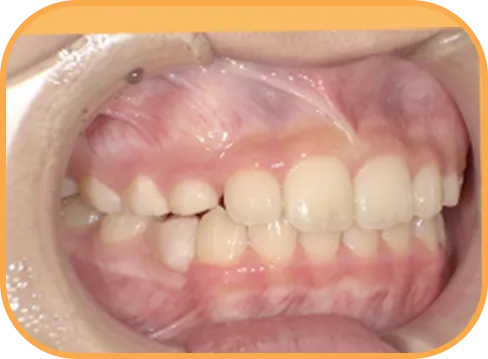

• Before

• 正 面

治療前正面からの歯の様子

• 上 顎

治療前上顎からの歯の様子

• 下 顎

治療前下顎からの歯の様子

• 右 側

治療前右側からの歯の様子

• 左 側

治療前左側からの歯の様子

主 訴

前歯がでている、噛み合わせが深い

治療内容

インビザライン・ファースト

治療期間

10か月

治療費(税別)

450,000円+診断料30,000円

リスク・副作用

• 親知らずの影響や加齢などによって、凸凹が生じる可能性があります。

• 治療の初期段階では痛みや不快感が生じやすくなりますが、1週間前後で慣れます。

• 顎の成長発育によって、噛み合わせや歯並びが変化する可能性があります。

• 状況により当初予定した治療計画を変更する可能性があります。